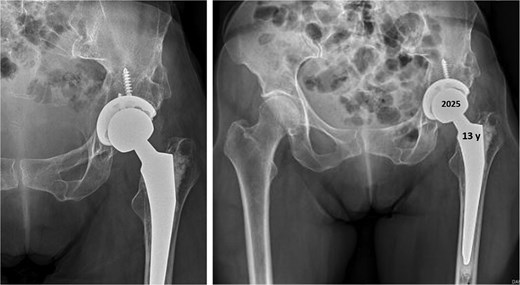

Twenty-eight years after triple osteotomy, the patient presented with painful end-stage osteoarthritis, with body mass index of 18. A hybrid cemented THA was performed using a standard posterolateral approach (Fig. 3). A cobalt-chrome femoral head was articulated with highly reticulated polyethylene liner. A press-fit cementless cup stabilized with two screws (Tylogy®, Zimmer) and a cemented straight femoral stem (Müller®, Zimmer) were implanted.

Anteroposterior radiographs of the pelvis 28 years after the pelvic osteotomy, showing advanced left hip osteoarthritis (Tönnis Grade V). A hybrid cemented total hip arthroplasty was implanted using a standard posterolateral approach.